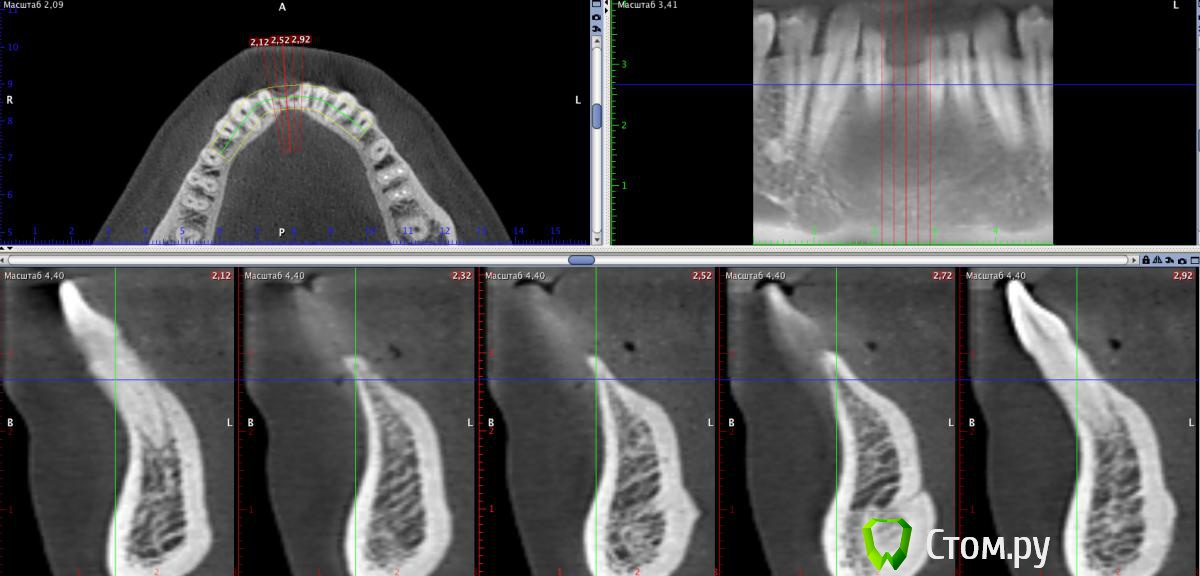

stommm Опубликовано 24 июня, 2014 Поделиться Опубликовано 24 июня, 2014 (изменено) Уважаемые коллеги, обратился пациент с желанием восстановить утраченные 41 и 26. На кт картина следующая: 41: по аксиальному срезу хочется добавить блок (ламинат) вестибулярно, но по боковым срезам кажется еще и язычно надо добавить26: удалить апексы, потом либо небно нарастить ширину тем же ламинатом, либо сделать синус и поставить имплант апикальнее. На картинке для сравнения нарисован имплант 4*10. Как бы вы поступили в такой ситуации? Может лучше заменить ламинаты ламинами и сделать мпк? Изменено 24 июня, 2014 пользователем stommm Ссылка на комментарий